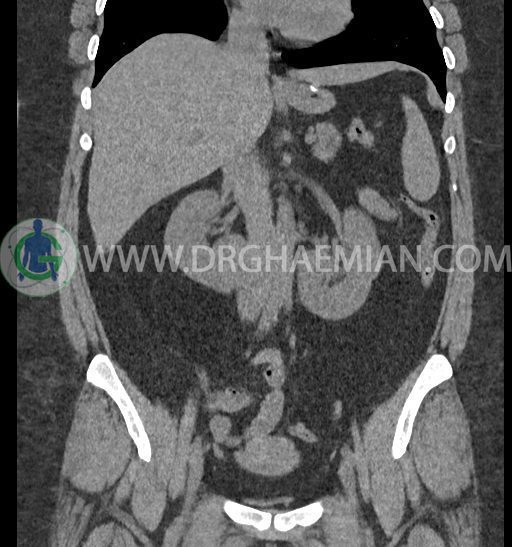

سی تی اسکن شکم و لگن با استفاده از اشعات ایکس تصاویر عرضی از ناحیه شکم و لگن ایجاد میکند. در این کیس کلیه نعل اسبی و سنگ کلیه مشاهده می شود.

در سی تی اسکن اسپیرال شکم و لگن بدون کنتراست (مولتی دیدکتور 16 با مقاطع ظریف و بازسازی های ساژیتال و کرونال) :

ضایعهای در کبد، کیسه صفرا، مجاری صفراوی، طحال، پانکراس و آدرنالها مشهود نیست.

-horseshoe kidney

-حداقل سه سنگ 5mm در کلیه راست و یک سنگ 3mm در کلیه چپ بدون شواهدی از هیدرونفروز